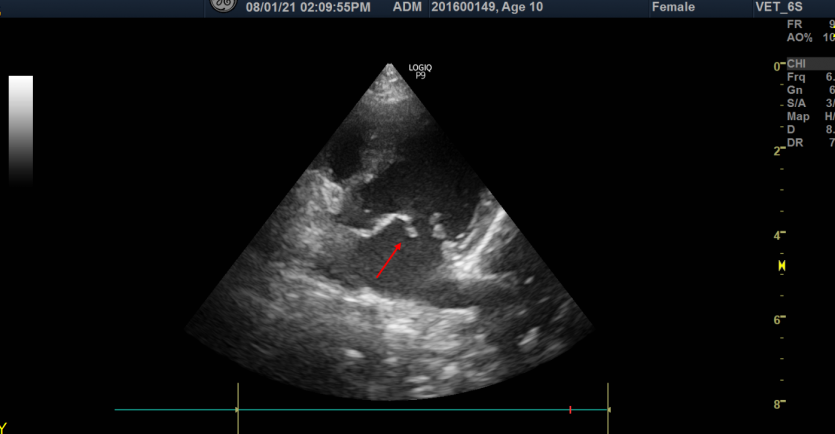

내원 후 흉부 방사선 사진 촬영과 심장 초음파 검사 진행

저희 잠실ON동물의료센터에서는 복슬이의 정확한 증상 파악을 위해 흉부 방사선 사진촬영과 심장 초음파 검사를 진행하였습니다.

갑작스러운 호흡곤란의 원인은 심장질환 중, 예후가 불량한 건삭 파열인 것으로 확인되었습니다.